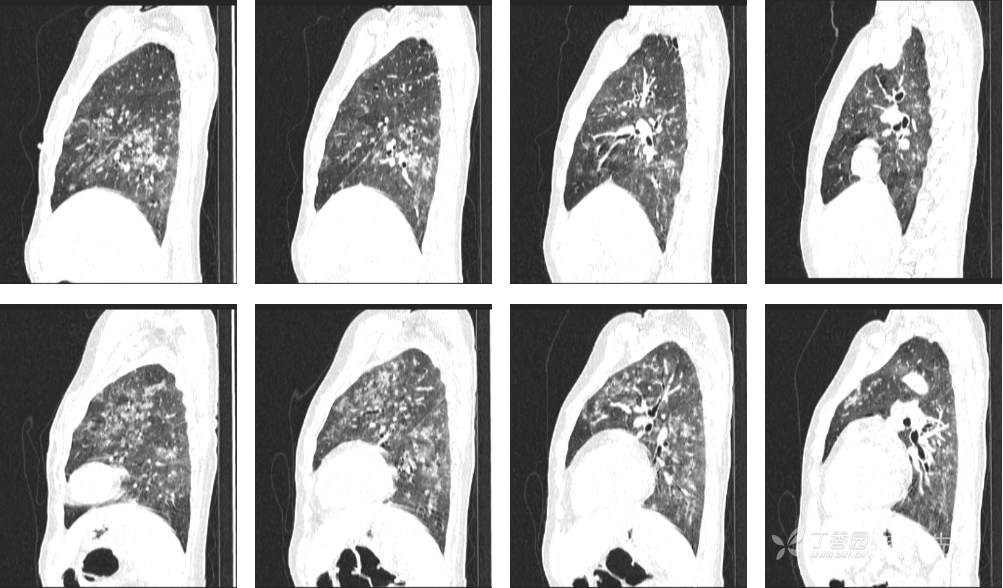

7月特别精彩病例|右肾移植术后咳嗽并气促20天,有重点病史,让诊断变简单|结果公布

主诉:咳嗽并气促20天

现病史:患者20天前无明显诱因出现咳嗽,咳白色粘痰,感活动后气促,在当地医院就诊,予以莫西沙星2周后未见明显好转,仍有活动后气促,无畏寒发热。今为进一步治疗,收住入院。患者自起病以来,患者精神食欲欠佳,大便正常,小便量少,体重无明显变化

既往史:右肾移植术后